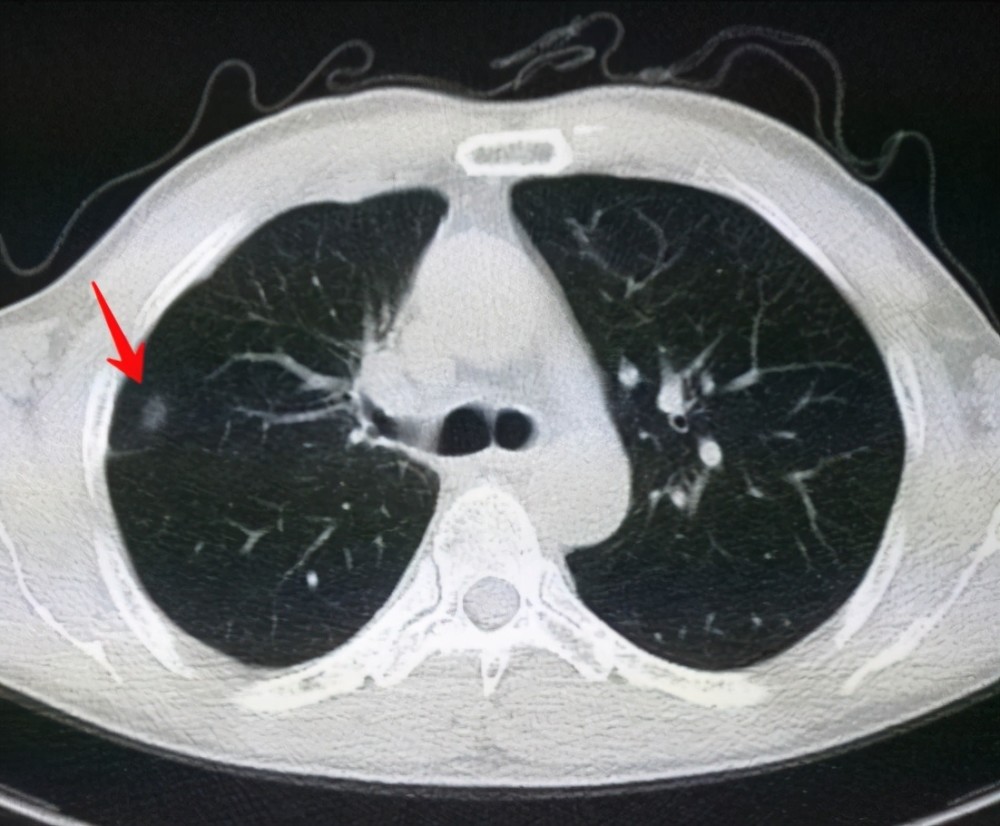

肺結(jié)節(jié)是一種常見的肺部疾病,其發(fā)病率逐年上升,雖然肺結(jié)節(jié)多數(shù)情況下是良性的,但也有可能惡化為肺癌,了解肺結(jié)節(jié)的形成原因?qū)τ陬A(yù)防和治療具有重要意義,本文將為您詳細(xì)解析肺結(jié)節(jié)的形成機(jī)制。

肺結(jié)節(jié)的形成原因

1、環(huán)境因素

環(huán)境因素是肺結(jié)節(jié)形成的重要原因之一,長期暴露于污染環(huán)境中,如空氣污染、化學(xué)污染等,可能導(dǎo)致肺部吸入有害物質(zhì),從而引發(fā)肺結(jié)節(jié),長期接觸石棉、硅塵等職業(yè)環(huán)境因素也可能增加肺結(jié)節(jié)的發(fā)病風(fēng)險。